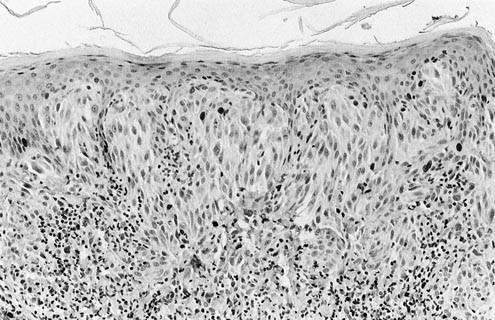

None of the common nevi showed more than 5% labeling for Ki-67, and all of them were completely nonreactive for p53 as well. The mean MIB-1 index was 0.5% in that group, with a range of 0 to 5% reactive cells (Tables 1 and 2). The majority of cases of CN (43 of 76 [57%]) failed to exhibit any nuclear staining. Likewise, SN demonstrated a very low Ki-67 index, ranging from 0 to 11% with a mean of 1.4% (Fig. 1); only one case of SN manifested more than 5% nuclear labeling. All SN likewise failed to label for p53. The results for LMMs and MCN were similar to those obtained in common nevi and SN; the average MIB-1 indices for those two forms of melanoma were 1.5% and 0.6%, respectively, and only 5% of LMMs and 4% of MCN were labeled for p53. The highest degree of both Ki-67 and p53 immunoreactivity was observed in NMMs. Seventy-eight percent of those tumors were p53 positive, and they had a mean proliferation index of 16.1% (Figs. 2 and 3). The only other group of melanocytic tumors with substantial p53 labeling (25%) was the SSMMs, in which an average Ki-67 staining index of 3.1% was obtained (Fig. 4). In aggregate, the proliferation indices of nodular melanoma and superficial spreading melanomas differed statistically from those of LMMs and melanomas arising in preexisting nevus (P <.05, χ2), but this obviously was due principally to the effect of data from the NMM group. Further corroboration of the latter point was gained from the observation that a statistically significant difference was also observed in the mean Ki-67 indices between SSM and NMM (P <.05, χ2). Conversely, p53 labeling was significantly and independently different for both the SSMM and NMM categories as compared with all other melanocytic lesions in the study (P =.035, χ2) (Fig. 5). Using a model with a 10% cutoff level for MIB-1 labeling and a 5% level for concurrent p53 immunoreactivity, 24 (75%) of the NMMs in this series could be correctly identified as in the vertical growth phase. In contrast, only five (8%) of the radial growth phase SSMMs showed similar findings in regard to the two markers being considered (Fig. 6). In the context of all melanomas in this study, the positive predictive value of the previously cited p53/Ki-67 threshold was found to be 83% for identification of the vertical growth phase.